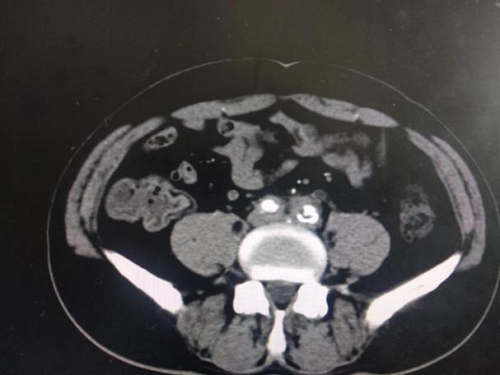

辅助检查:完善泌尿系CTU示腹主动脉下段、双侧髂总动脉周围见软组织影环绕,可见延迟强化,于左侧髂总动脉水平病变与左输尿管分界不清,相应水平左输尿管狭窄,以上输尿管,肾盂、肾盏扩张积水,腹腔、腹膜后未见明显肿大淋巴结。(如下图1-4)

(图1-4泌尿系CTU示考虑腹膜后纤维化累及左输尿管致尿路梗阻)